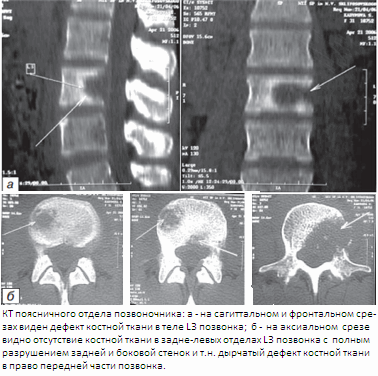

Использование КТ (компьютерной томографии) позволяет уточнить степень и характер поражения костной ткани, в том числе дуг и отростков позвонков, что невозможно при традиционной рентгенографии, а также выявит костную деструкцию с секвестрами на ранних стадиях. Таким образом, использование КТ при туберкулезном спондилите показано: в случаях, когда на обычных рентгенограммах и томограммах деструкция не выявляется, а на МРТ имеется патологическое изменение сигнала от позвонков; для выявления или уточнения деструкции костных элементов задней позвоночной колонны (дуг, отростков, дугоотростчатых суставов); для уточнения характера разрушений в сложных для рентгенологического исследования областях - субокципитальной, шсйно-грудной, пояснично-крестцовой; при недостаточности рентгенологической информации о соотношении деструктивных костных полостей с просветом позвоночного канала, паравертебральными тканями и соседними органами; в послеоперационном периоде для оценки сращения трансплантатов с костным ложем, радикальности выполненного оперативного вмешательства и выявления рецидивов паравертебральных абсцессов.

На основании проведенного анализа рентгенограмм и КТ и МРТ позвоночника при туберкулезном спондилите по характеру деструкции выделены 3 основных вида: 1) очаговая деструкция в телах позвонков; 2) образование межтелевой костной каверны с секвестрами или казеозными массами, периферические отделы тел при этом сохранены и образуют своеобразную «костную коробку» вокруг полости деструкции; 3) плоскостная контактная деструкция, когда смежные отделы тел разрушены равномерно по всей площади. По глубине деструкции тел выделено 4 варианта разрушения позвонков: 1) тела позвонков разрушены поверхностно и до 1/3 высоты; 2) тела позвонков разрушены на 1/2 или 2/3 высоты (встречался наиболее часто); 3) субтотальное и тотальное разрушение позвонков; 4) деструкция по типу кариеса. При вовлечении в процесс большого числа позвонков наблюдалось сочетание видов и вариантов деструкции. В редких случаях атипичного течения туберкулезного спондилита характер деструкции не укладывался в указанные виды.

Инфильтрация в позвоночном канале выявлялось у 45(32,1 %) больных. На рентгенограммах абсцессы хорошо выявлялись в грудном отделе позвоночника, где они видны на фоне воздушной легочной ткани. Забрюшинные абсцессы выявлялись по косвенному признаку расширения контуров m.iliopsoas major, когда достигали значительных размеров. Невозможно было увидеть абсцесс мягких тканей спины и небольшие паравертебральные абсцессы в поясничном отделе позвоночника. Контуры абсцессов и их соотношения с окружающими органами на рентгенограммах и томограммах удавалось определить не всегда. КТ и МРТ в равной степени хорошо выявляли абсцессы, их камеры, соотношения с позвонками и окружающими органами и тканями, особенно после внутреннего контрастирования. На ранней стадии формирования абсцесса отмечалась инфильтрация жировой прослойки вокруг тела позвонка. Преимущество МРТ — возможность многопроекционного исследования, что позволяло выявить соотношения абсцессов не только с окружающими тканями, но и связь их между собой. Комплексная оценка изменений костной структуры, выявляемых на рентгенотомограммах и КТ, и патологических изменений сигнала на МРТ, давала представление о морфологических изменениях в позвоночнике и о фазе туберкулезного спондилита.